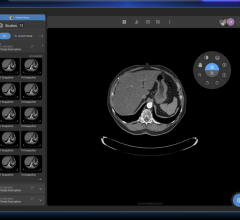

Even before the pandemic began to spread, the idea of offering radiologists the flexibility to work from home was trending. When COVID-19 enforced social distancing and new work behavior, it kicked this trend into high gear. Working from home helps limit exposure to the virus while still allowing radiologists to read as if they were on-site. The first challenge is creating home reading solutions that are the same level of quality, security and performance radiologists get from a medical workstation in the hospital reading room. The second challenge is getting them set up in a timely manner.

Barco and VisionTek partnered to develop a solution specifically designed for remote radiology reading that tackles both challenges. Together, they are undertaking the issues of technology compatibility and performance, security and patient privacy, as well as quality and compliance. Their home read solution has attracted immediate attention and early adoption in the hospital community.

The VisionTek Thunderbolt 3 Mini eGFX Enclosure comes in a sleek and portable design that discretely sits on a desk, or hidden away, to handle graphic intensive medical scan applications. Combined with a pre-installed Barco MXRT-display controller, VisionTek’s Thunderbolt 3 Mini eGFX Enclosure can accelerate the most demanding medical scan software programs.

“This configuration is seamlessly deployable and mirrors the hospital reading environment providing the same diagnostic confidence and medical compliance maintained within hospital walls,” reported Mike Sklar, VP Healthcare Sales for the Americas at Barco. “It’s paired with Barco’s QAWeb Calibration and Monitoring Software, which is the industry's first and only web-based service for high-grade Quality Assurance.”

"VisionTek’s Mini eGFX enclosure powered by Barco MXRT series graphics boards and diagnostic displays allow Radiologists to remotely read scans in the safety of their home office." stated Michael Innes, President, VisionTek Products, LLC. “VisionTek is very proud to play a small part in technology innovation that impacts some of the most critical healthcare applications within the radiology community.”